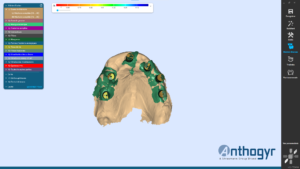

La planification implantaire a été réalisée sur le logiciel SMOP. Les empreintes ont été superposées avec le cone beam du patient.

Les implants ont été posés virtuellement, ce qui a permis au praticien d’évaluer la possibilité d’extraire, implanter et mettre en charge immédiatement lors d’une même séance.

Une fois la planification validée, un guide implantaire SMOP a été dessiné et imprimé (imprimante STRATASYS poly-jet avec précision à 16 microns ).

Le praticien a choisi de poser 2 implants Thommen en FULL GUIDED.

2ème étape : pose des implants grâce au guide SMOP

Positionnement fidèle a la planification et comblement des hiatus péri-implantaires à l’aide d’un biomatériau xénogénique.